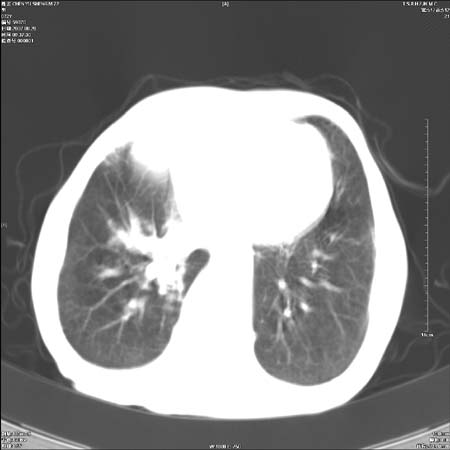

男性,72岁,既往肺结核,今复查。无前片对比。

右侧中央型肺癌伴中叶不张可能性大,建议增强扫描.右上肺陈旧性肺结核.慢性支气管炎伴肺气肿.右侧少量胸腔积液.

中心性肺癌肺转移

右侧中央型肺癌伴中叶不张可能性大,建议纤支镜检查.右上肺陈旧性肺结核.肺气肿。

典型右肺中心型肺癌

右侧中央型肺癌伴肺不张可能性大,建议增强扫描.右上肺陈旧性肺结核.慢性支气管炎伴肺气肿.右侧少量胸腔积液.

右肺中心型肺癌

右侧中央型肺癌.上肺陈旧性肺结核.

1右侧中央型肺癌伴中叶不张2右侧少量胸腔积液3右上肺陈旧性肺结核

1.右肺中心性肺癌并右肺中叶综合征2。右侧胸腔少量积液3。右肺上叶结核球已钙化,4。慢支伴肺气肿

右侧中央型肺癌伴中叶不张可能性大,建议纤支镜检查.右上肺陈旧性肺结核.肺气肿。

右侧中央型肺癌伴中叶不张可能性大,建议增强扫描.右上肺陈旧性肺结核.慢性支气管炎伴肺气肿.右侧少量胸腔积液.

右侧中央型肺癌伴中叶不张

右肺中央型肺癌伴右肺中叶不张。

右上肺陈旧性肺结核。

支持右肺中心型肺癌并中叶不张,右上肺陈旧性肺结核钙化,右侧少量胸腔积液。

支持右侧中央型肺癌伴中叶不张可能性大,建议增强扫描.右上肺陈旧性肺结核.慢性支气管炎伴肺气肿.右侧少量胸腔积液.

右侧中心型肺癌可能性大.肺气肿.胸腔积液.

支持 1右侧中心型肺癌伴中叶不张2右侧少量胸腔积液3右上肺陈旧性肺结核4双肺局限性肺气肿

1,右侧中央型肺癌.

2,右上肺陈旧性肺结核.

1.右侧中央型肺癌伴中叶不张,建议纤支镜检查.

2.右上肺陈旧性肺结核.

3.肺气肿。

4.右侧少量胸腔积液.

右侧中央型肺癌伴中叶不张并纵隔淋巴结增大,建议增强扫描.右上肺陈旧性肺结核.慢性支气管炎伴肺气肿.右侧少量胸腔积液。

右肺中心型肺癌并肺不张,陈旧性肺tb.慢支,肺气肿.

陈旧性肺结核.慢性支气管炎伴肺气肿,中央型肺癌伴中叶不张。

右侧中央型肺癌伴中叶不张可能性大;右上肺陈旧性肺结核.慢性支气管炎伴肺气肿

陈旧性结核是存在,但真正致命的却是右侧中心型肺癌。